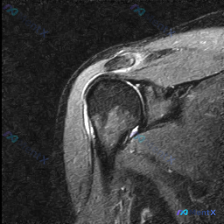

看到一份肩部MRI T2序列冠状位的病例资料,用户观察到的核心是“盂唇病变”。先放影像分析的重点内容: 1. 冈上肌腱在肱骨大结节附着点区域呈明显高信号,肌腱变薄、变细,有回缩迹象 2. 肩峰下-三角肌下滑囊区域可见长条状高信号影,提示滑囊积液 3. 盂唇形态相对自然,未见明确的巨大撕裂征象 大家觉...

整理了一个有意思的运动损伤病例,拿出来大家一起讨论一下: 患者是20岁女子大学排球运动员,5天前打完排球后出现左肩钝痛,睡觉压到、抬举或外展左臂时疼痛加重。 生命体征:体温37.0℃,其余基本正常。 查体:左肩无肿胀畸形,前外侧触诊轻度压痛;左臂主动外展仅到70°就受限,被动外展活动范围正常,但会诱...